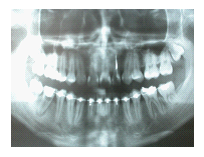

43歲女性病人,如圖1A所示。病人由其他醫師轉診來拔除左下顎嚴重蛀牙的第二大臼齒與阻生智齒,理論上如果拔除此第二大臼齒後,必須以人工植牙重建之,但是病人有經濟上的考量,因此與病人討論過後,決定將同時欲拔除的 阻生智齒移植入第二大臼齒齒槽,雖然病人年紀稍大,仍值得一試,圖1B 是術後一個月的X光片,由於病人年紀較大,智齒在植入缺牙區域時,已同時作根管治療,圖1C是術後四個月的X光片,根管內充填的是Vitapex(Ca(OH)2),圖1D是術後一年四個月後的X光片,智齒牙根尖的骨頭已經全部再生回來,而且牙根無黏連的情形,臨床上牙齒動搖度小於1,牙周組織健康,而其前面的第一大臼齒情況良好,咬合正常。

圖1B

圖1C

圖1D